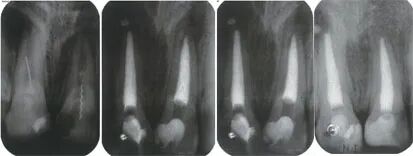

根管马达怎么修根管内器械分离的影响因素_https://www.jmylbn.com_新闻资讯_第4张

3  术前片(左上1~2图)可见两颗上颌中切牙根管内都存在分离器械,很可能是因为基于近远中病损建立的开髓孔,无便利形所致。规范开髓后,分离器械被取出并完成了根管治疗。右上图和左下图为3个月和12个月的复诊片显示病变逐渐愈合